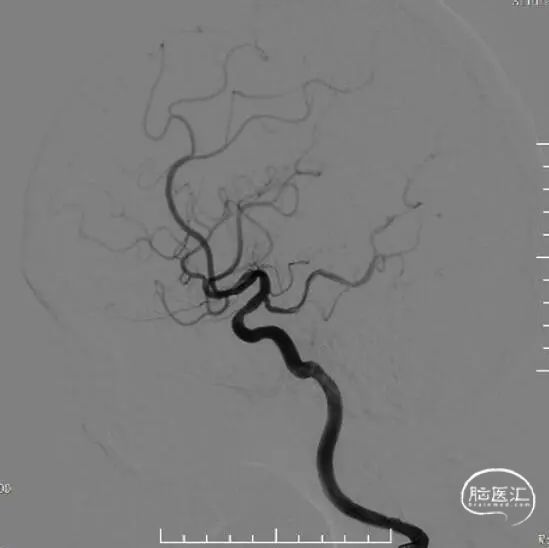

脑血管造影:右侧大脑中动脉M1段局部瘤样突起,远端重度狭窄,考虑右侧大脑中动脉M1段夹层动脉瘤。

右侧颈内动脉正侧位和右侧大脑中动脉工作位造影。

右侧椎动脉正位和侧位。

左侧椎动脉正位和侧位。

左侧颈总动脉正位和侧位。

治疗之前3D和工作位(测量病变处近远端血管管径,M1近端1.9mm,M1远端1.7mm)。